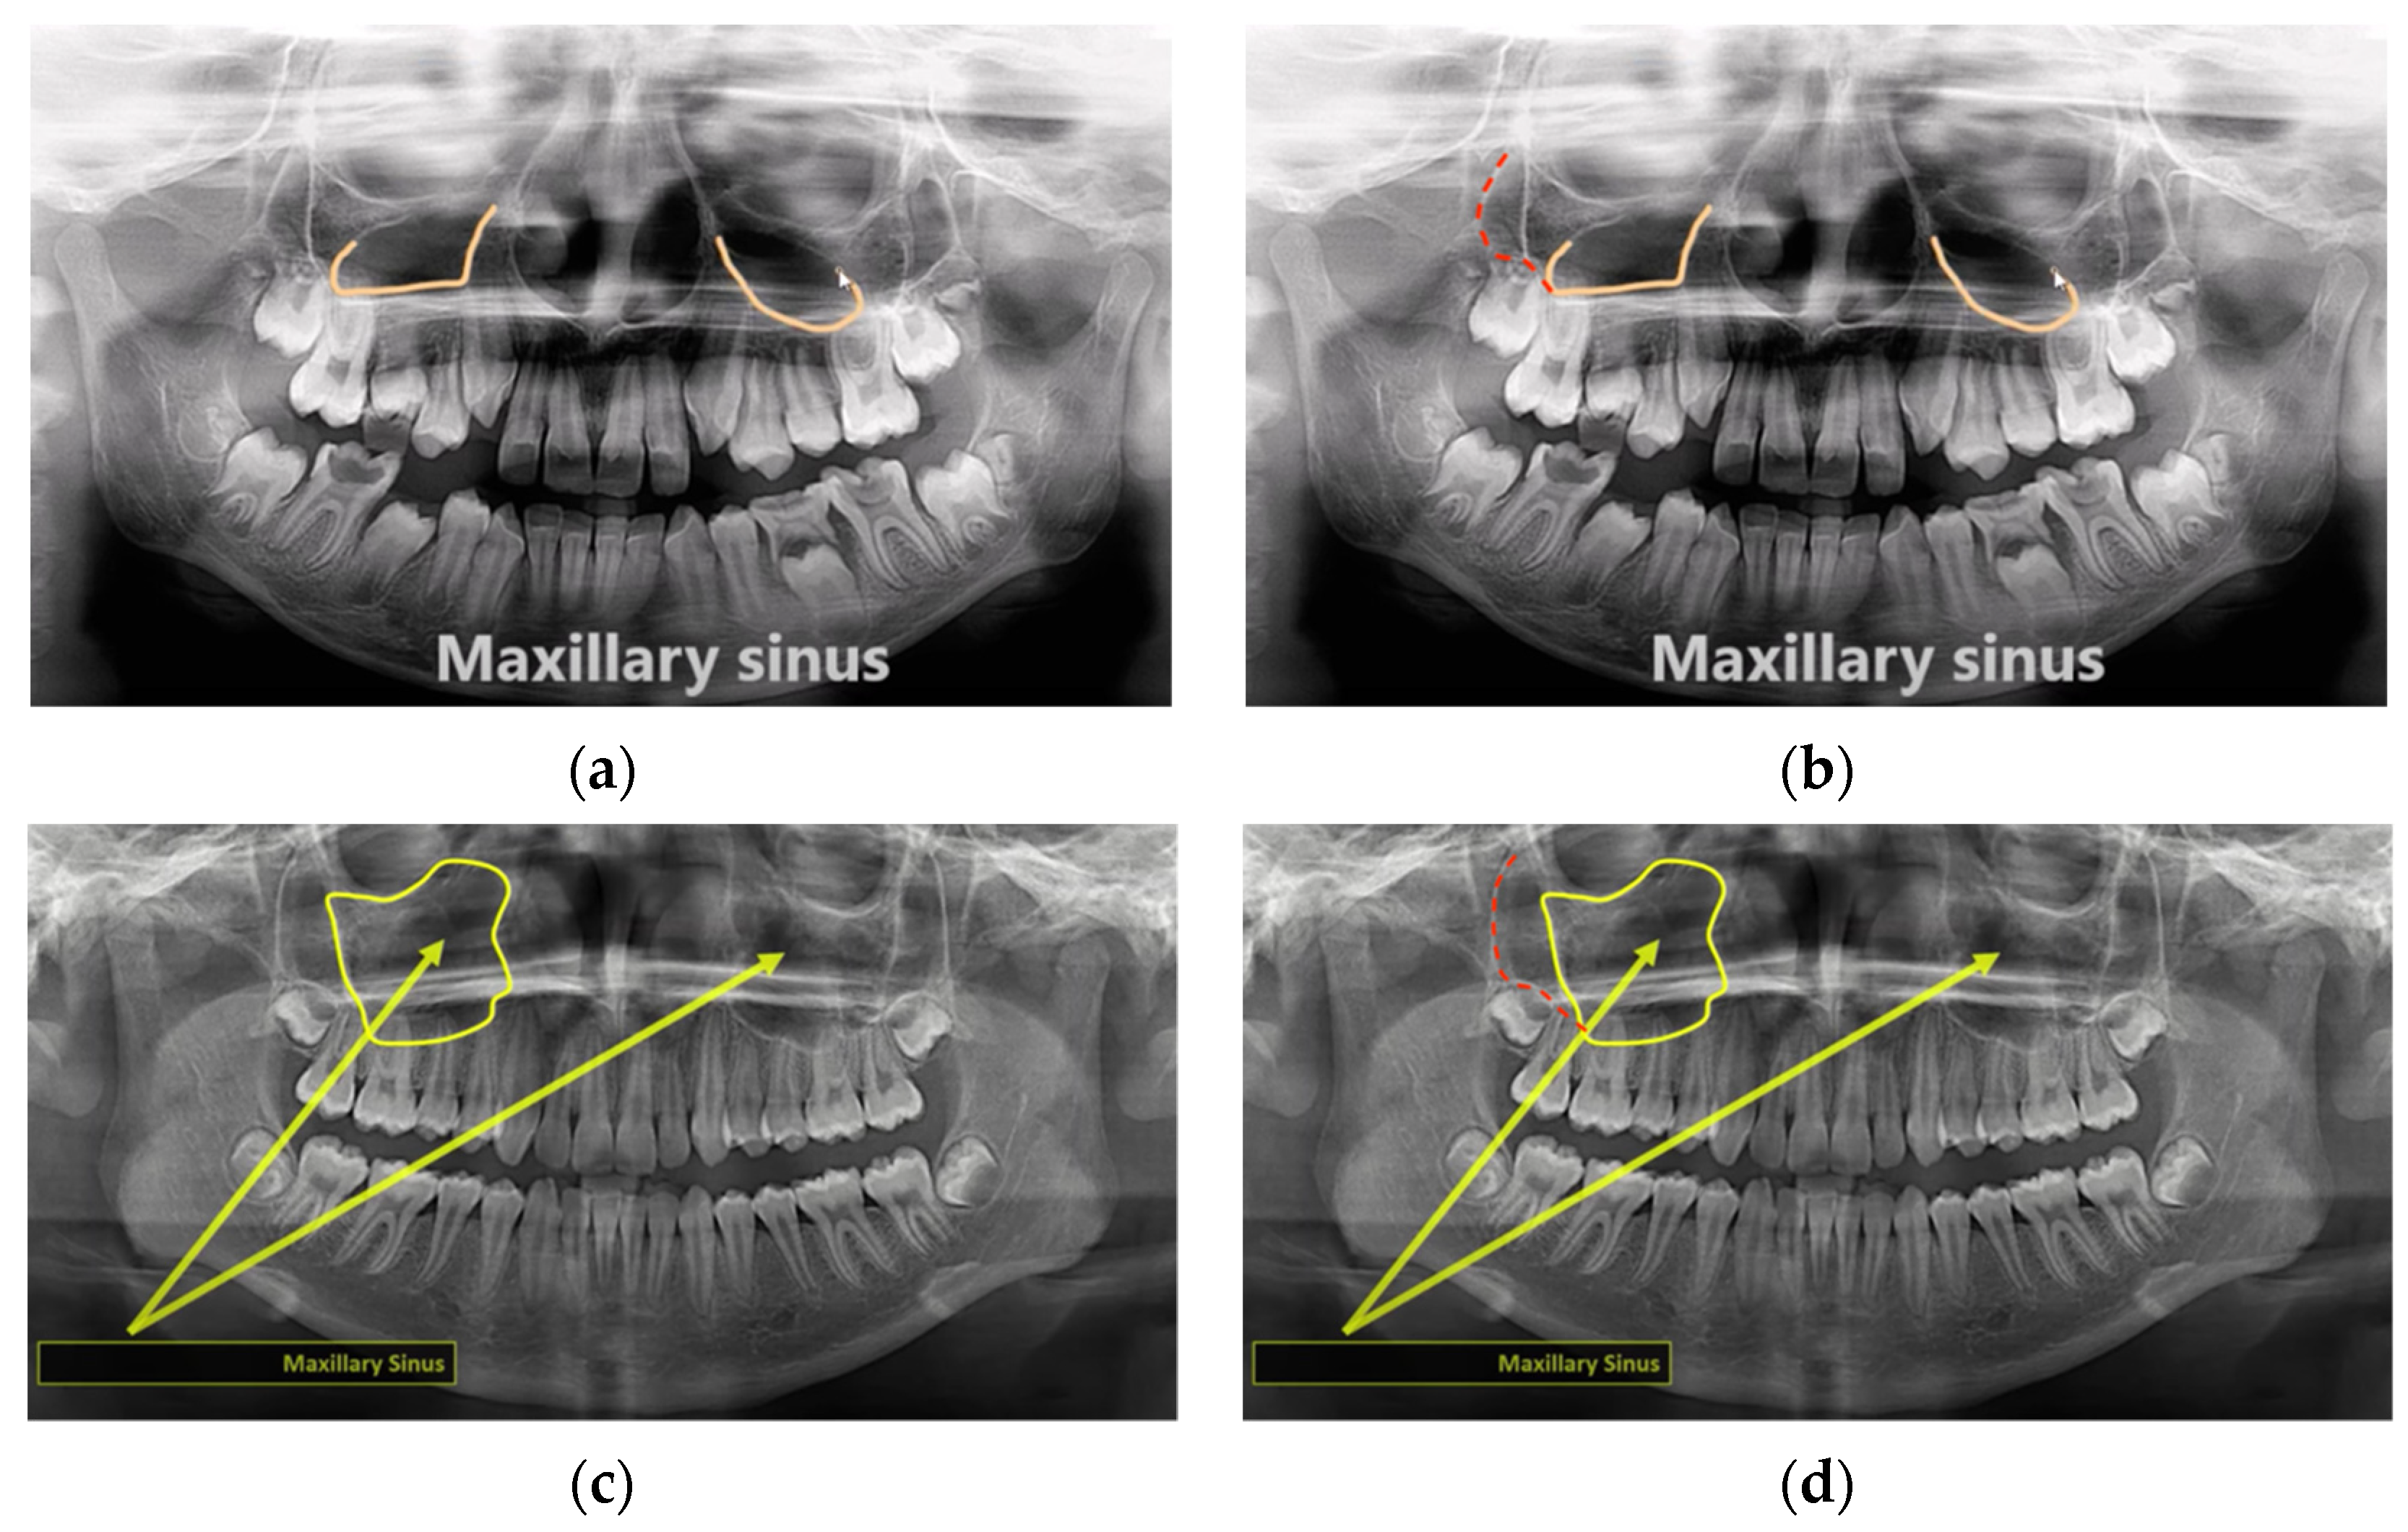

3. Results

4. Discussion